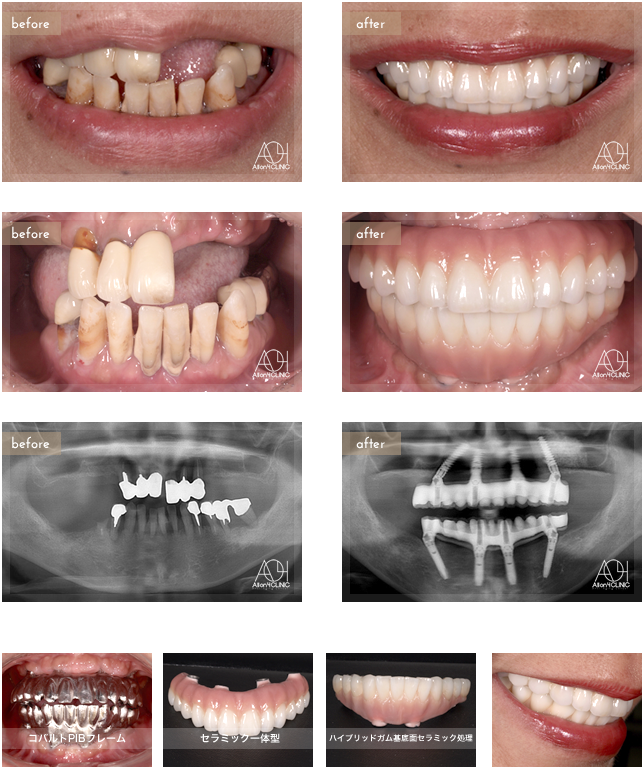

Age : 61

Sex : Female

Treatment :

- Maxilla All-on-4

- Under All-on-4

上顎はNobel Active、下顎Speedy Groovy インプラントを埋入。上顎上部構造はコバルトPIBフレームセラミック一体型。下顎はコバルトPIBフレーム(歯肉:ハイブリッドガム基底面セラミック接着処理 歯:ハイブリッド)